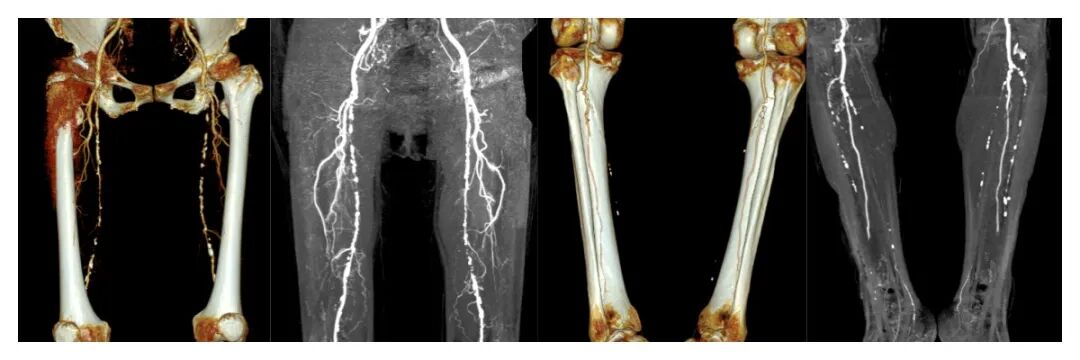

术前影像

CTA检查确诊双下肢动脉硬化闭塞症,双下肢血管弥漫性硬化,股动脉、胫前动脉、腓动脉均中重度狭窄,下肢供血严重不足,再不治疗恐面临截肢风险!